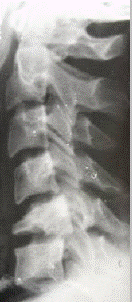

В качестве иллюстрации приводим рентгенологическую картину формирования костного блока у больного В., 21 лет, которому выполнен спондилодез на двух уровнях по поводу нестабильного перелома С6

позвонка (см. рисунок 1).

а) б) в)

Рис.1. Больной В., 21 лет. Д–з: нестабильный перелом тела С6

позвонка.

а – при поступлении; б – 7 дней после операции; в – 11 недель после операции.